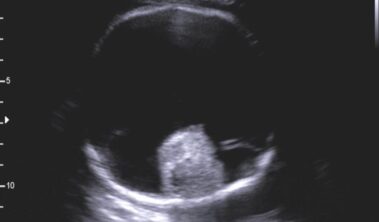

Holoprosencefalia alobar

Se caracteriza por marcados alteraciones en la línea media del encéfalo y/o malformaciones faciales.

Hallazgos radiológicos:

- Fusion completa de los hemisferios cerebrales

- Ausencia de la fisura interhemisferica y de la hoz cerebral

- Agenesia del cuerpo calloso y de la comisura anterior

- Holoventriculo, quiste dorsal

- Ausencia de septum pellucidum

- Los ganglios de la base de tálamos pueden estar diferenciados, funcionado o ausentes